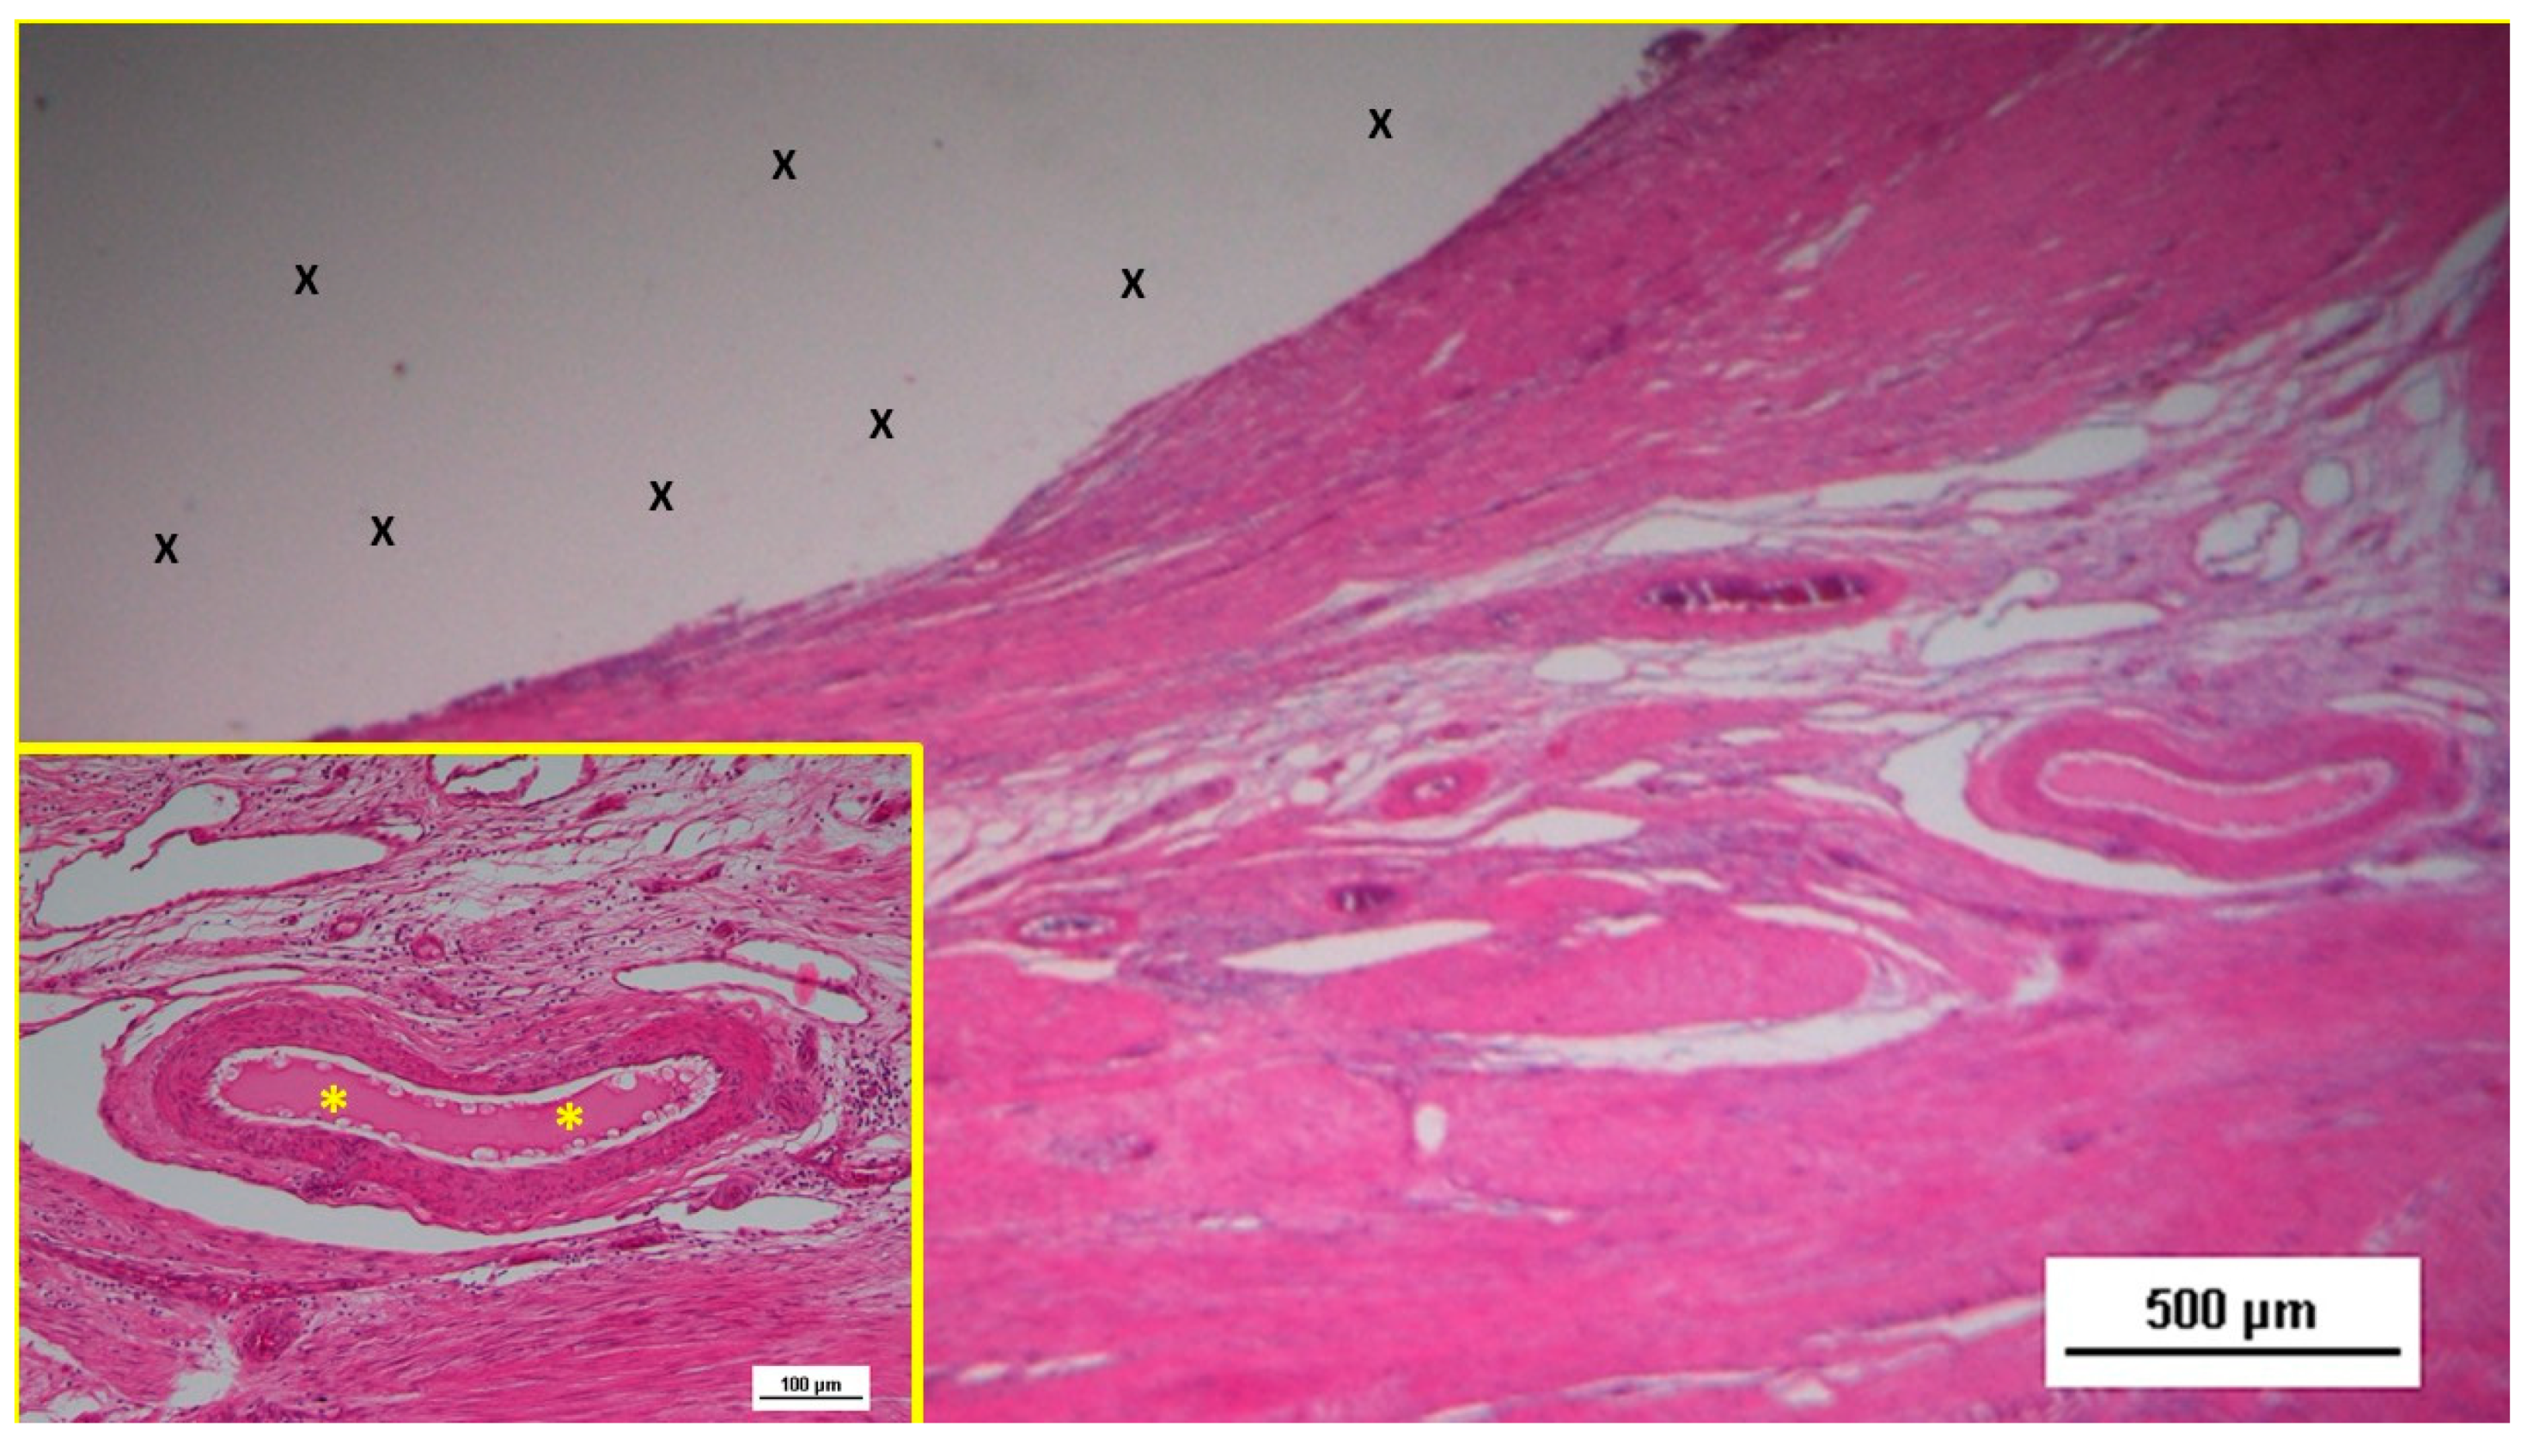

6-8 months post-implantation (long-term stage), there was a complete absence of inflammation, and the newly formed arteries and veins demonstrated full structural maturation across all components (Figure 11, Figure 12, Figure 13, Figure 14 & Figure 15).

Figure 14. Biopsy sample excised six months post-implantation from the 3D scaffold of the S&S device. The microphotograph shows multiple arterial structures (targeted elements) and veins (white spots) within a slack connective matrix, situated between two areas of muscle tissue (red-stained). No inflammatory reaction is evident near the S&S device fabric (X). The inset (lower left corner) provides a magnified view of an artery, displaying all three mature layers with a blood-filled lumen (*). HE 25X (main image) and 100X (inset).